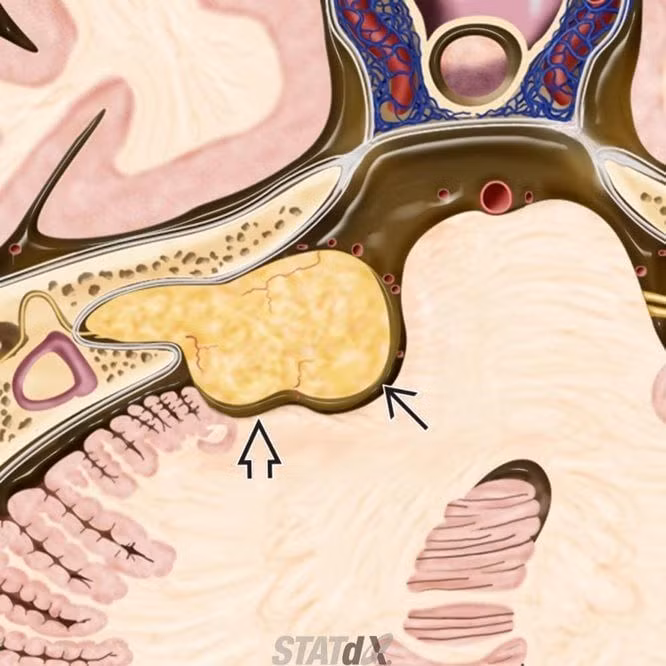

u dây thần kinh tiền đình - ốc tai có hình kem ốc quế

Schwannomas tiền đình, còn được gọi là u thần kinh thính giác, là những khối u tương đối phổ biến phát sinh từ dây thần kinh tiền đình- ốc tai (CN VIII) .

Schwannomas tiền đình là các khối u lành tính, thường phát sinh từ đoạn ống tiền đình của dây thần kinh tiền đình-ốc tai gần điểm chuyển tiếp giữa tế bào thần kinh đệm và tế bào Schwann. Trong hơn 90% trường hợp, những khối u này phát sinh từ vị trí chia nhánh phía dưới của dây thần kinh tiền đình. Ít hơn 5% trường hợp phát sinh từ phần ốc tai của dây thần kinh tiền đình- ốc tai.